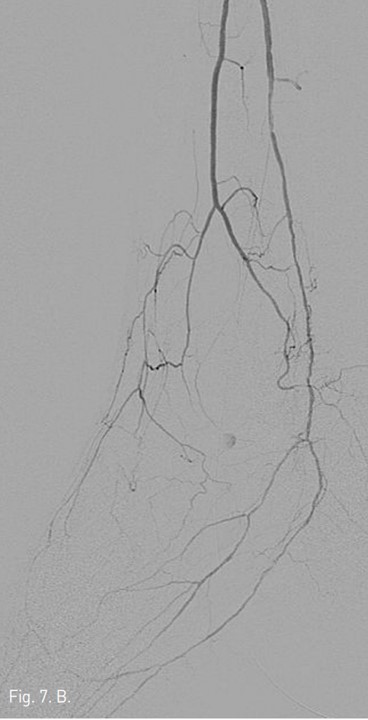

우총대퇴동맥을 통해서 5Fr catheter 내로 goose neck snare를 insertion하여 GT Guide wire를 잡아빼낸 후(Fig. 5A), 이를 다시 SV 5 Guide wire (Cordis, Miami, USA)로 교환하였다 (Fig, 5B). 3mm/10cm balloon을 우총대퇴동맥에서부터 삽입하여 우측 후경골동맥에 대해 subintimal angioplasty를 시행하였고 (Fig. 6), final arteriogram 상 우측 비골동맥과 우측 후경골동맥의 혈류는 완전 재개통되었다 (Fig. 7A 7B). 우측 SFA 협착 부위에 대해서 6mm/12cm SMART stent를 삽입한 후 시술을 마쳤다. 일주일 뒤 시행한 doppler 검사는 시술 이전과 크게 차이가 나지는 않으나, 발의 온도는 시술전보다 따뜻해져서 임상적인 호전을 보였다.

Fig. 7. B

Fig. 7. Final angiography shows complete recanalization of arterial flow in both left posterior and left peroneal arteries.